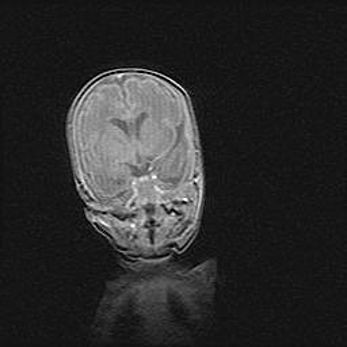

Открытая гидроцефалия.

Возраст: 6 месяцев 15 дней

Вес: 6200 г

Пол: женский

Окружность головы: 41 см

Срок гестации: 38 недель

Гидроцефалия головного мозга у новорожденных – это скопление избыточного количества цереброспинальной жидкости в головном мозге. Ее избыточное скопление в мозге приводит к патологическому расширению желудочков мозга (четырех полостей, расположенных в глубине белого вещества мозга, заполненных цереброспинальной жидкостью и связанных узкими проходами).

Открытый тип гидроцефалии (сообщающаяся) наблюдается тогда, когда нарушен механизм всасывания ликвора в системный кровоток. При этом типе причиной заболевания чаще всего является перенесенные ранее инфекции (например: менингит),  либо же наличие крови в субарахноидальном пространстве.